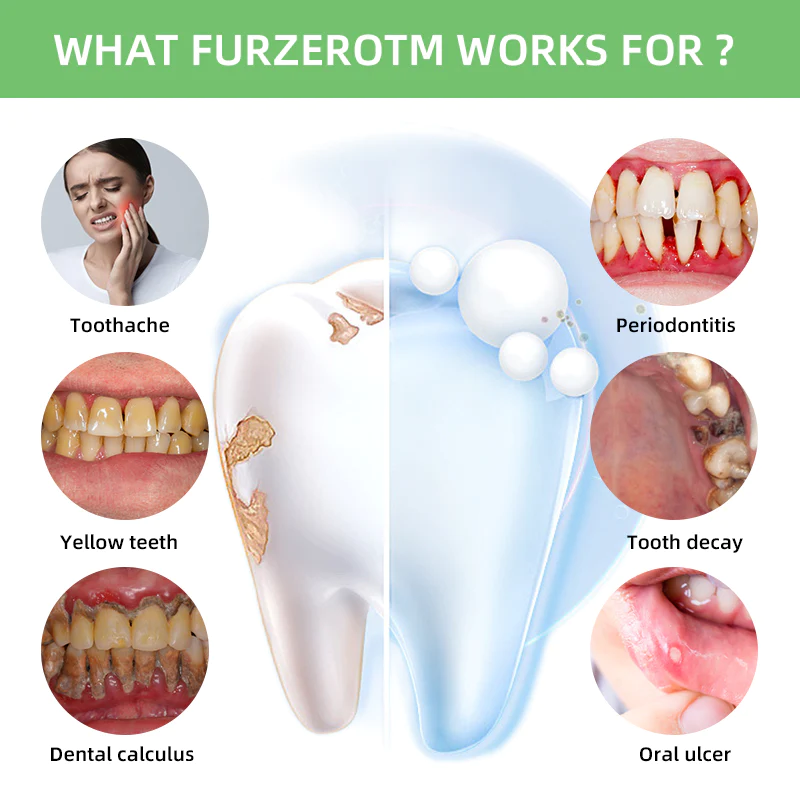

What Can FURZERO Do For You?

Whiten Teeth

Relieve And Prevent Mouth Sores

Mouth ulcers are usually caused by bacterial erosion, which makes us suffer from pain and prevents us from eating normally. FURZERO™ Herbal Brightening Oral Repair Foam can help you kill the bacteria in your mouth and heal mouth ulcers.

Prevent Cavities

FURZERO™ Herbal Brightening Oral Repair Foam can help you kill bacteria that penetrate deep into the alveolar and root canal, stimulate the restorative formation of dentin, and help repair tooth decay. For severely necrotic cavities, it can stimulate the gums to produce new tooth germs and promote the growth of new teeth.

Remove Calculus

Calculus is calcified dental plaque that inflames the gums, which can lead to bone loss, loose teeth, tooth sensitivity, etc. FURZERO™ Herbal Brightening Oral Repair Foam can help eliminate dental plaque and remove stubborn calculus attached to teeth, making your teeth white and healthy again.

Stimulate The Regrowth Of Lost Teeth